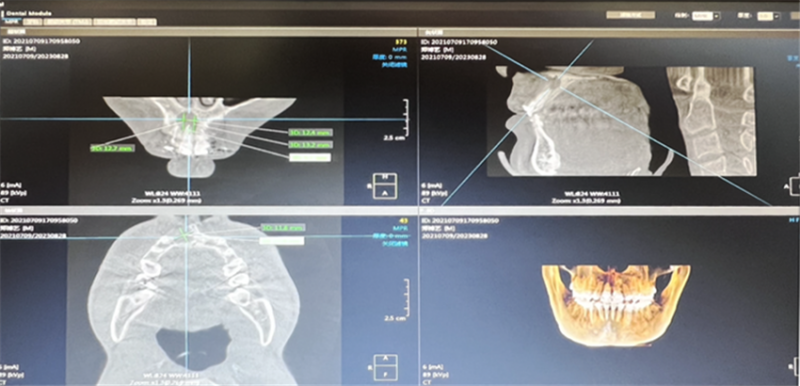

术前口腔CBCT。(翻拍图片)

该患者因“上前牙外伤后2年,牙龈反复红肿伴渗出2月”到巫山县中医院口腔科就诊,并诊断为11牙慢性根尖周炎并根端囊肿。

巫山县中医院口腔科常樨林主任与烟台山医院支医专家田鸿旭医生对患者的临床资料和影像学资料进行了详细分析,确定了“11牙根管治疗+根端囊肿摘除术+位点保存术+引导骨再生手术”的治疗方案。在征得患者及其家长的同意后,田鸿旭医生主刀,为患者实施了“11牙根管治疗+根端囊肿摘除术+位点保存术+引导骨再生手术”。手术过程顺利,术后即刻CBCT检查显示:根端囊肿完全清除且骨填充致密。术后10天,患者的创区愈合良好,顺利拆线。